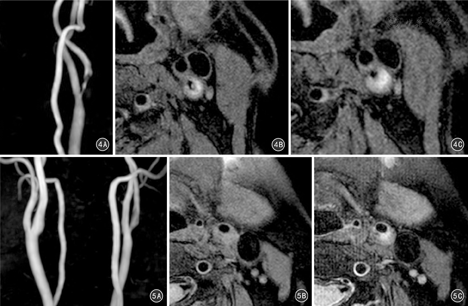

与病理检查比较,MRI检查颈动脉粥样硬化斑块中钙化、斑块内出血、富含脂质的坏死核检出率偏低,而纤维帽表面破裂的检出率偏高,但差异均无统计学意义(P值均>0.05),见表4及图4、图5。

同时,本研究结果显示与病理组比较,MRI组颈动脉粥样硬化斑块中富含脂质的坏死核、斑块内出血、钙化检出率偏低,而纤维帽表面破裂检出率偏高,但差异均无统计学意义(P值均>0.05)。以上结果提示,高分辨率MRI对颈动脉粥样硬化斑块成分能有较好识别,尤其对富含脂质的坏死核检出率接近病理结果,令人鼓舞,但这需要良好的设备基础和经验丰富的协作团队。笔者在实际操作中亦发现,目前MRI对颈动脉粥样硬化斑块检测需要耗时25~30 min左右,噪音较大,空间狭小,部分患者难以坚持,且稍有运动,图像因伪影就难以研判,给斑块的识别带来困难。因此,研发新的高分辨率MRI优选序列,进一步改善噪声率、空间分辨率、图像的信噪比以及采集速度,将是未来的发展方向。总之,本研究结果表明高分辨MRI多序列技术相结合,能够较为准确地定性、定量分析颈动脉斑块的负荷、成分特征,可用于斑块的风险评估,对缺血性脑卒中的病因诊断、治疗选择以及判断预后均具有非常重要的临床价值。